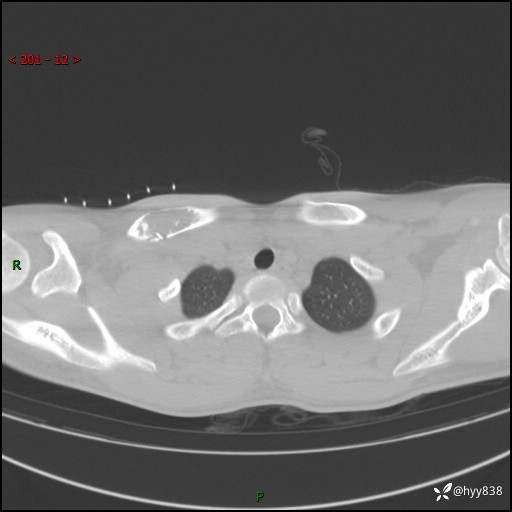

CT